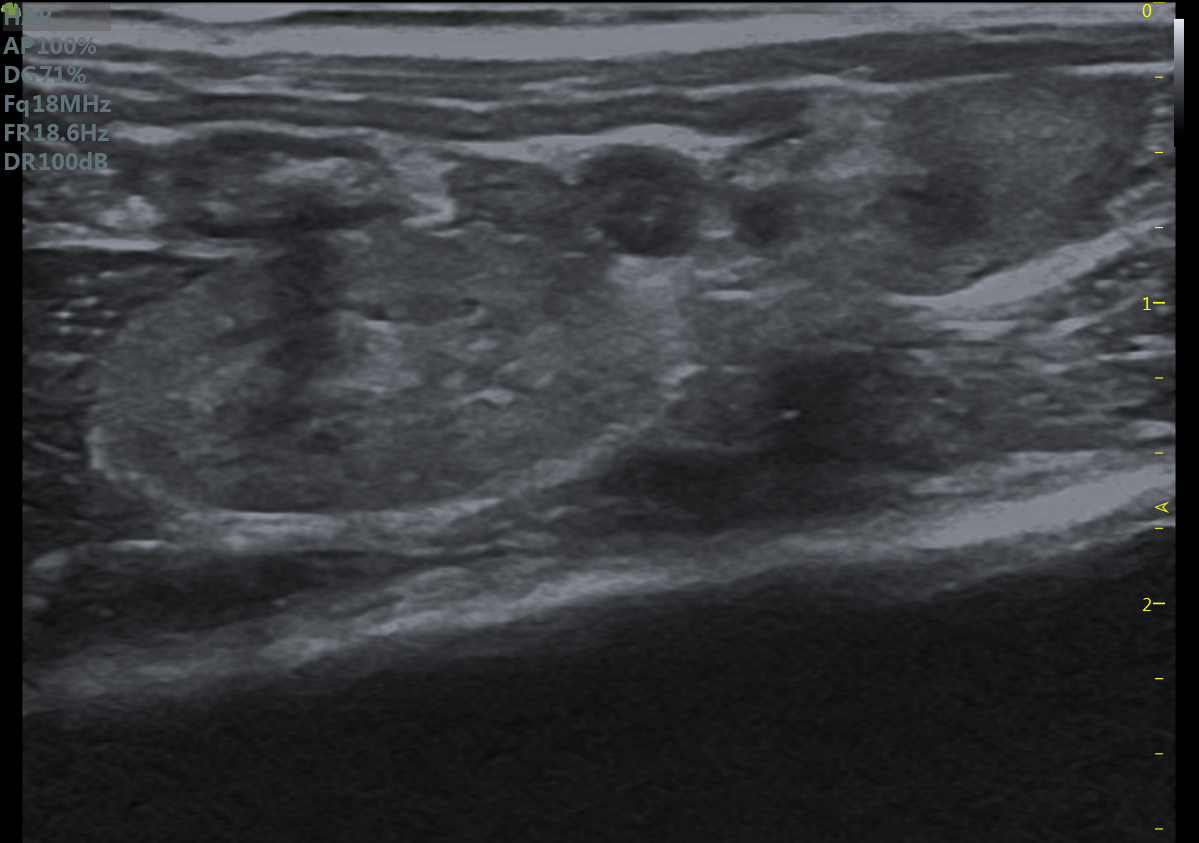

23MHz高频探头,优秀卓越的浅表显影

RF Flow充盈不外溢 Xcen超高频浅表显影